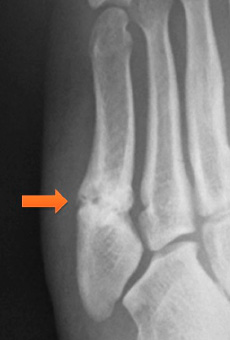

右足の小指を骨折された方の写真です。

医師の同意を頂き、接骨院でも施術が可能となります。

リハビリをして、スポーツ復帰にむけて頑張りましょう!!